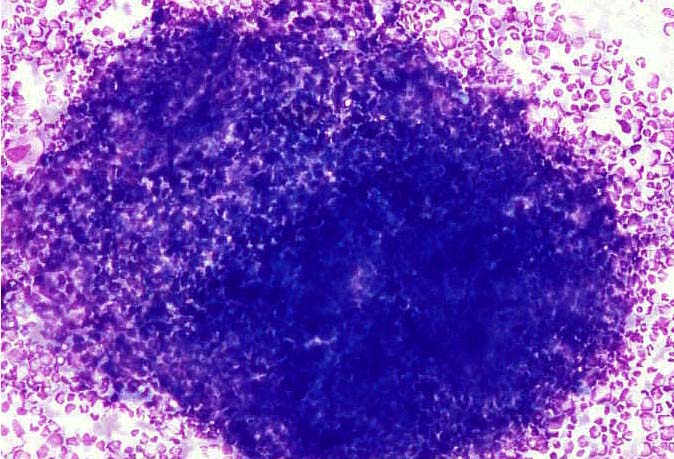

診断材料 骨髄

染色 メイ・ギムザ

光顕的所見 骨髄では過形成がうかがえる。

【MG.×100】